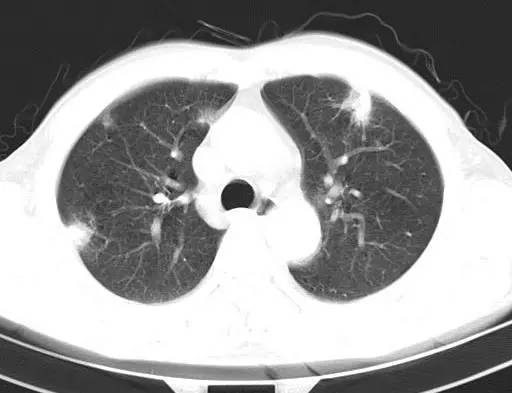

治疗前CT(图1-8):两肺胸膜下散在多发斑片状、结节状伴空洞影,边缘欠清晰。